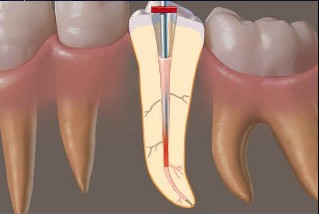

一、顯微根管治療:利用顯微鏡移除金屬釘柱及根管治療

利用顯微鏡將金屬釘柱移除,再以鎳鈦超彈性器械修形根管(圖三),待患者的症狀都恢復正常後再利用熱塑型馬來膠將根管緻密封填(圖四),圖五為根管治療後的情況,與圖二相比,可見正門齒及側門齒已徹底封填。